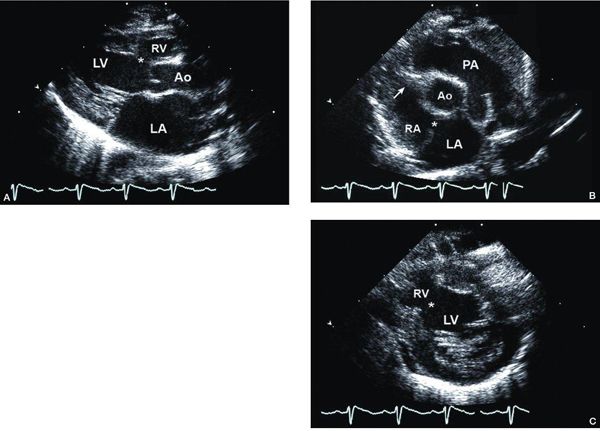

Parasternal long axis Parasternal long-axis scans typically demonstrate a small anterior RV and a large posterior LV (Fig. 12.4A). This scan plane also provides excellent views of the ventricular septum. The size and position of the VSD should be noted (see Fig. 12.4A). The position and origin of the great arteries are confirmed. In the presence of transposed great arteries, the arteries appear parallel in their proximal course from the ventricles, with the posterior vessel (PA) bifurcating early (Fig. 12.5A). If the VSD is present in the outlet portion of the septum, anterior deviation of the septum (seen most commonly with normally related great arteries) may produce subpulmonary obstruction. Posterior deviation is seen more often with transposed great arteries. Muscular ridges or membranes can also cause ventricular outflow obstruction and should be evaluated from multiple imaging planes. Anterior angulation of the transducer toward the patient’s left shoulder may bring the right ventricular outflow tract (RVOT) into view. Doppler and color Doppler evaluation of the gradient from the LV to RV and into the RVOT should be used to provide information about the degree of restriction, either to the PA (for an estimation of the PA pressure) or to the anterior aorta in transposition.

Figure 12.4. Tricuspid atresia with normally related great arteries; parasternal views. A: Long-axis view showing small anterior right ventricle (RV) and dilated posterior left ventricle (LV). There is a muscular ventricular septal defect (asterisk). B: Short-axis view at the cardiac base demonstrating normally related great arteries, an atretic tricuspid valve (arrow), and a secundum atrial septal defect (asterisk). C: Short-axis view at the level of the mitral valve (M) demonstrating the dilated LV communicating with the hypoplastic RV through a large muscular ventricular septal defect (asterisk). Ao, aorta; PA, pulmonary artery (Video 12.3).

Parasternal short-axis view The parasternal short-axis view is useful for further characterization of the hypoplastic RV and VSD and position of the great arteries (Figs 12.4B and 5B). Left ventricular function should be evaluated. Scanning apically from the base of the heart toward the midventricular level, the right ventricle is seen in front of the dominant, large LV (Fig. 12.4C). In addition to orthogonal subcostal views, the size of the RV and the anatomy of the VSD can be assessed in the short-axis plane (Fig. 12.4C). The presence of additional VSDs should be assessed with both imaging and color Doppler. Pulsed-wave Doppler interrogation can provide an estimation of the gradient between the LV and RV as well as aid in assessing the restrictive VSD. Scanning superiorly toward the base of the heart to the level of the great arteries will again confirm their arrangement. If transposed, both great vessels are seen in short-axis, represented by two semilunar valves seen in the same imaging plane (Fig. 12.5B). In transposition, one can evaluate whether the anterior aorta is located rightward (d-transposition, more common) or leftward (l-transposition, less common).

Figure 12.5. Tricuspid atresia with transposed great arteries; parasternal views. A: Long-axis view showing the parallel orientation of the great arteries classically seen in transposition, with an anterior aorta (Ao); posterior pulmonary artery (PA) originating from the dilated left ventricle (LV). B: Short-axis view at the cardiac base showing both semilunar valves in short-axis at the same level, again consistent with transposition of the great arteries. The aortic valve (Ao) is hypoplastic and located anterior and slightly rightward, whereas the pulmonary valve (PA) is dilated and located posterior and leftward. LA, left atrium (Video 12.4).